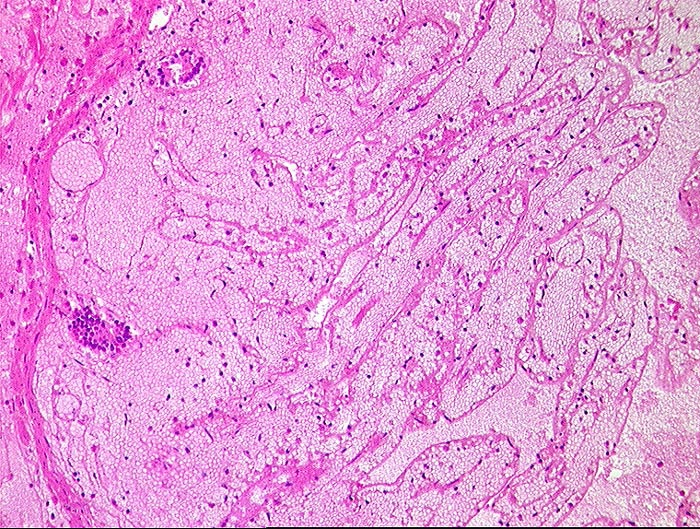

Mesenterialinfarkt

vaskulär / Durchblutungsstörung

Dünndarm

Makroskopie

Pathologischer Befund